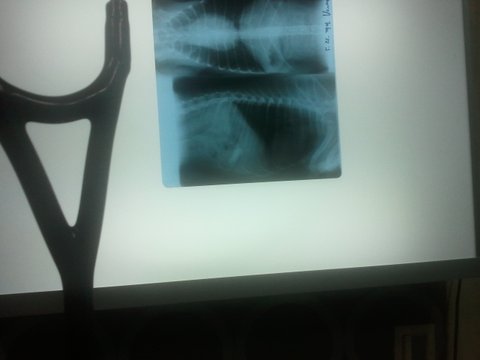

이젠 괜찮겠지?했는데 ..보이세요?위속에 좀 큼직한게 걸려서 거의 매일 아침마다 토하드라구요